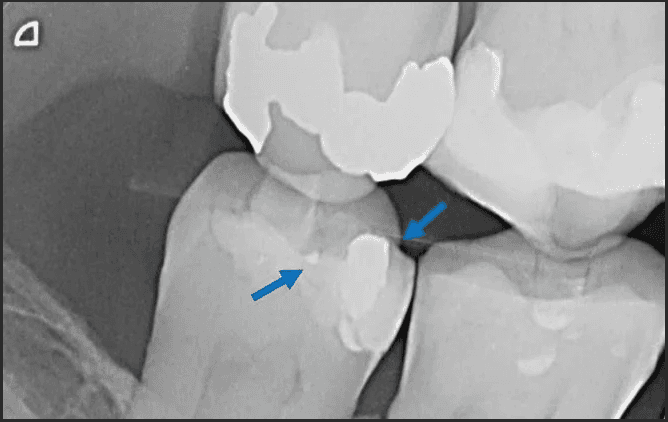

An X-ray was taken and sure enough, it was observed that there was amalgam left underneath by the previous practitioner, rather than it being completely removed. The blue arrows on the x-ray indicate where the residual amalgam was.